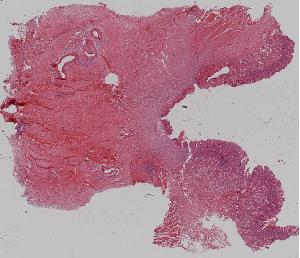

8.肉芽组织

低倍视野